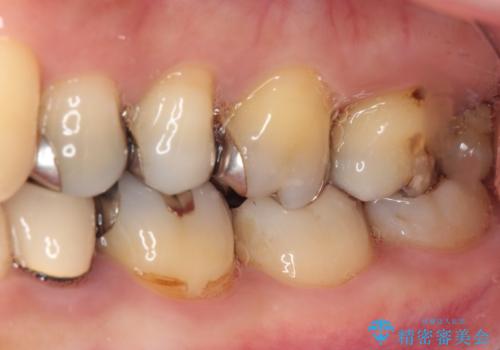

知覚過敏の症状はなくなり、希望通りの白い歯になったと、患者様は大変満足されました。